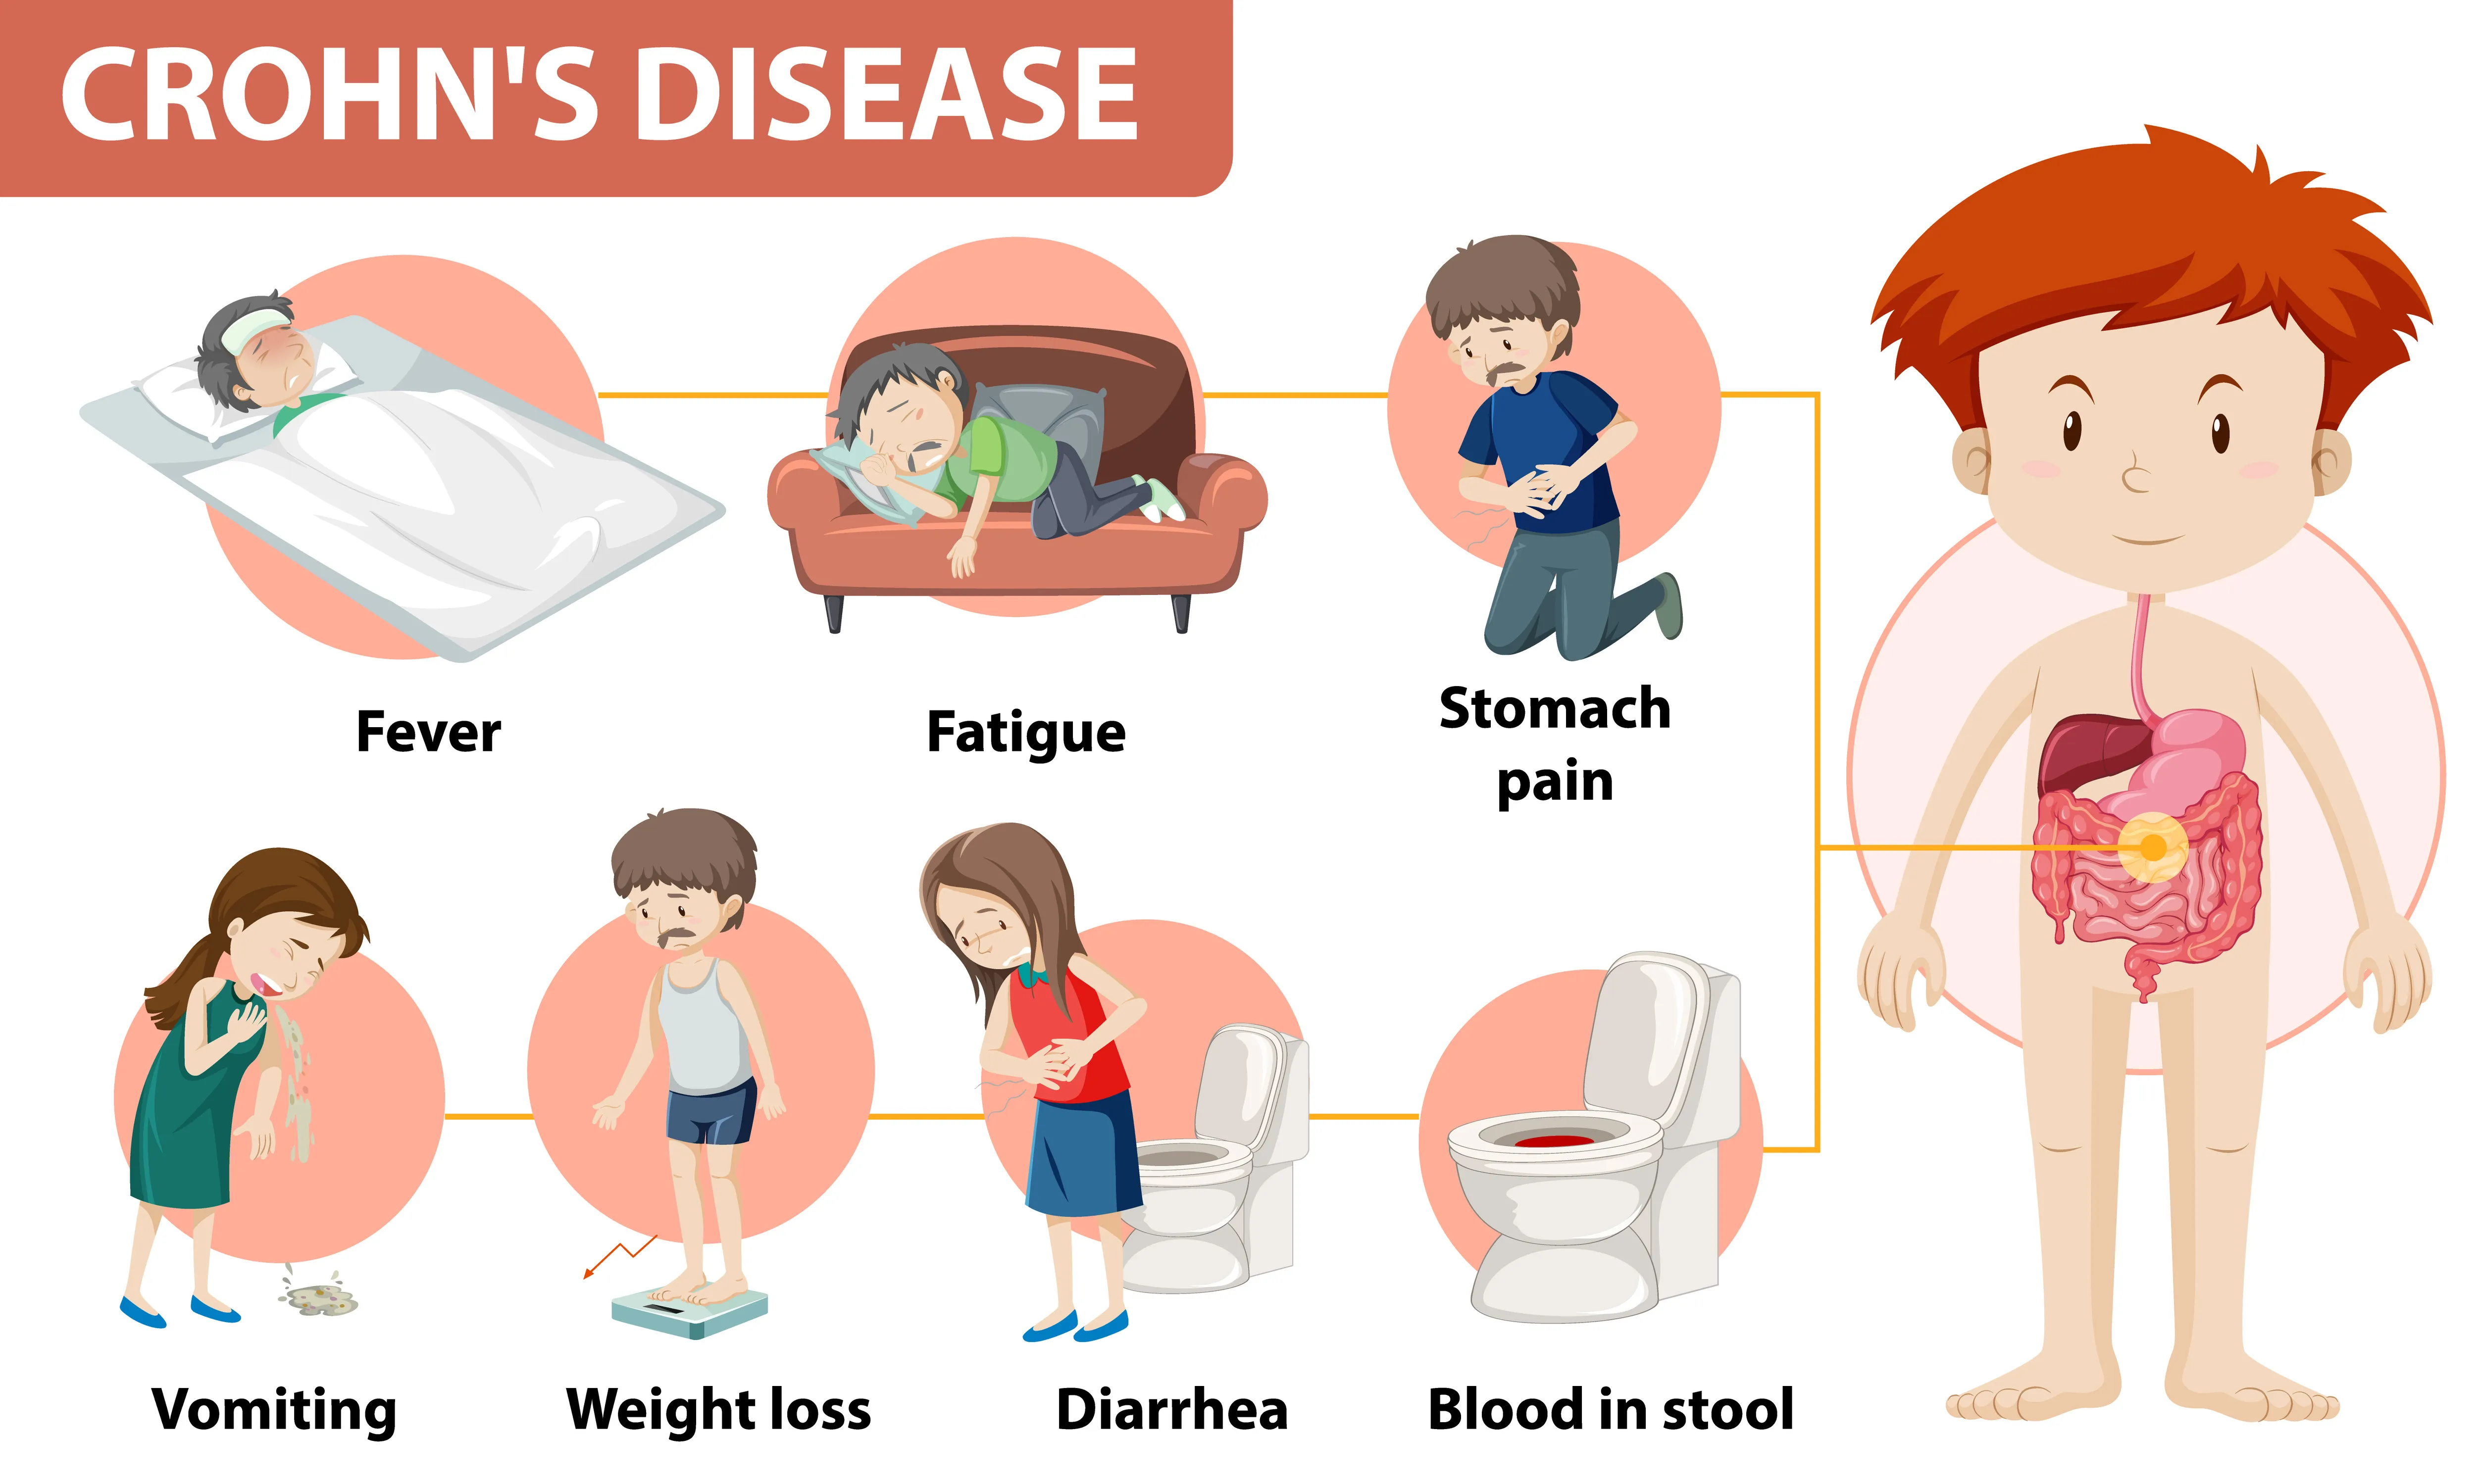

クローン病

クローン病(CD:Crohn's Disease)は、消化管に慢性的な炎症が起こる原因不明の炎症性腸疾患で、難病指定を受けている病気です。

口から肛門まで、消化管であればどこにでも起こる可能性がありますが、小腸や大腸に多く見られます。

10代〜20代の若年者に発症しやすいとされ、男女比は2:1で、男性に多い病気です。

同じ炎症性腸疾患である潰瘍性大腸炎と同様に「活動期(症状が強く現れる時期)」と「寛解期(症状が治まっている時期)」を長期間にわたって繰り返し、肛門にも病変ができやすいことが知られています。

クローン病と潰瘍性大腸炎は、症状が似ているものの、治療法は大きく異なります。

適切な治療のためには、大腸カメラ検査による詳しい検査が欠かせません。

主な症状

- 腹痛

- 持続的な下痢

- 血便・粘血便

- 体重減少

- 疲労感

- 裂肛(切れ痔)

- 痔瘻(あな痔)

- 肛門周囲膿瘍

- 肛門皮垂